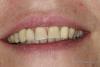

MaxDok Опубликовано 10 августа, 2013 Поделиться Опубликовано 10 августа, 2013 Слишком вестибулярно , отсюда коронка кажется слишком объемной . На времянке чуть больше места под сосочки оставил бы . Ссылка на комментарий

simpsons Опубликовано 11 августа, 2013 Поделиться Опубликовано 11 августа, 2013 Ранее был удален 1,3 так как устал быть в связке с имплантом на 1.2...короче скол ниже уровня десны на 3-4 мм. Убрали, поставили 4,2*13 АльфаБио (SPI).Временный абатмент,коронка.Сформировали десну, инд.абатмент (Церек) платформа немецкая, коронка пресс.Все....Такое ощущение что в "жигули поставили магнитолу от БМВ"! Как по мне,то здесь нужен комплексный подход! 1 Ссылка на комментарий

an_ver Опубликовано 12 августа, 2013 Автор Поделиться Опубликовано 12 августа, 2013 Такое ощущение что в "жигули поставили магнитолу от БМВ"! Как по мне,то здесь нужен комплексный подход!Емко сказано))) нравиться.По мне так же.Пац-ка не тянет по финансам Ссылка на комментарий